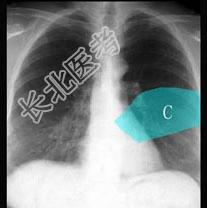

- 单项选择题在图所示正常胸部X线影像图像上,该英文字母所代表的肺段为 ( )

A、尖段

B、后段

C、尖后段

D、舌叶上段

E、前段